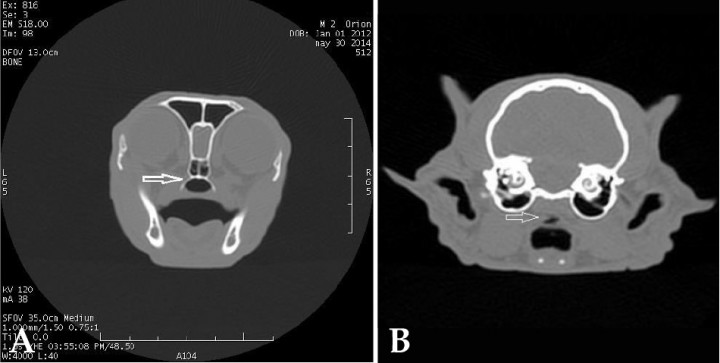

Por los resultados de las radiografías y para valorar al completo las vías respiratorias, localizar la lesión y el alcance de la misma, se realiza una TC. Se utiliza un TC GE-Brivo 325, helicoidal de 3ª generación, multicorte (2 cortes/rotación). El estudio de TC se lleva a cabo con el animal sedado con una combinación de midazolam (0,3 mg/kg i.m.) y dexmedetomidina (15 μg/kg i.m.). El estudio se realiza en secuencial con cortes de 1 mm y 1,5 mm entre cortes. El informe describe un escaso engrosamiento de mucosa nasal con imagen de paladar blando elongado, así como áreas pulmonares compatibles con restos de proceso neumónico. Se recomienda resección de parte del paladar blando. La figura 3A muestra la porción nasofaríngea de nuestro caso y la 3B cómo se observaría una estenosis nasofaríngea mediante TC. Se realiza un cultivo bacteriano y fúngico de los exudados respiratorios con resultado negativo.

<p>Imagen de TC en ventana de huesos y plano transversal. (A) En nuestro caso, se observa un área de la nasofaringe de diámetro normal (flecha). (B) En una TC diagnóstica, se observa un estrechamiento caudal a nivel de nasofaringe (Cortesía de Diagnosfera).</p>

Imagen de TC en ventana de huesos y plano transversal. (A) En nuestro caso, se observa un área de la nasofaringe de diámetro normal (flecha). (B) En una TC diagnóstica, se observa un estrechamiento caudal a nivel de nasofaringe (Cortesía de Diagnosfera).